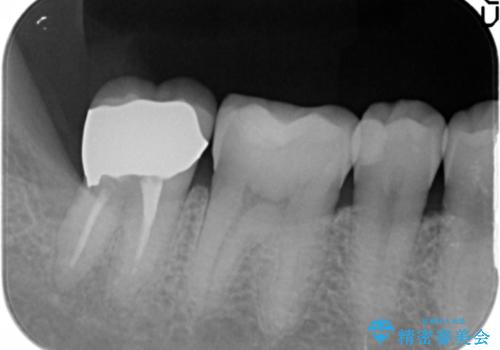

精査したところ、右下の一番奥の歯(右下7)に歯肉縁下に及ぶ深いう蝕を認めました。

神経がない歯であり痛みが出ないことから、自覚症状がほとんどなくう蝕が大きく進行してしまったと考えられます。

銀歯を除去し、歯周外科処置(右下7遠心の骨整形及びディスタルウェッジ)を行った後にメタルボンドクラウンによる補綴を行いました。